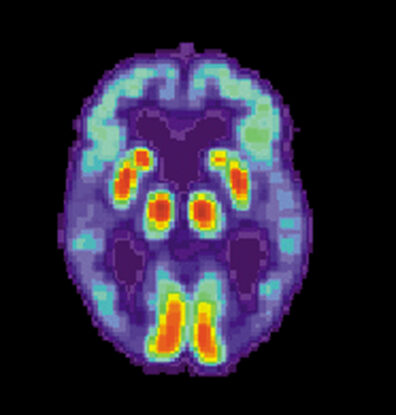

Dr. Suchy-Dicey and IREACH Director Dr. Dedra Buchwald have previously carried out brain imaging and cognitive testing and collected clinical histories in the same group of participants. To better understand the pathogenesis of Alzheimer’s disease, the new phosphorylated tau data will supplement this existing information. The new data will be examined in association with evidence of atrophy in targeted brain regions and with cognitive profiles of mild impairment and dementia. Future work will test for additional biomarkers and evaluate the prognostic utility of various biomarkers before the onset of dementia.